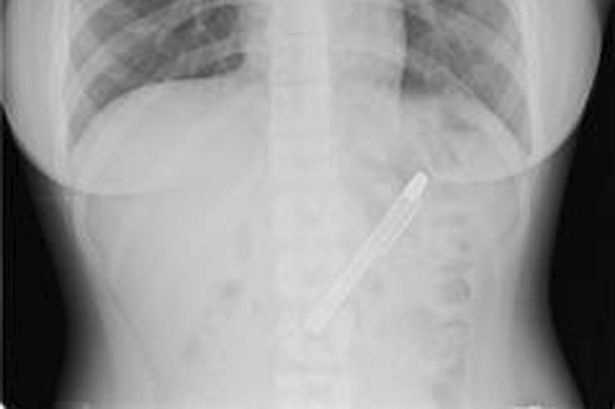

Tenía un dolor terrible en la panza que no la dejaba comer y, como no podía aguantar más y el dolor continuaba, decidió ir al hospital. Después de hacerle una serie de pruebas se toparon con una pluma estilográfica, que estaba ahí desde hacía nada menos que seis meses.

La radiografía que le hicieron en el hospital de Taipei, en Taiwán, no dejaban dudas que la lapicera estaba ahí y la estudiante no tenía la menor idea de cómo había llegado ahí. Según comentó, puede que la introdujera en su organismo el día que celebró la fiesta de fin de exámenes en la que se pasó de copas.